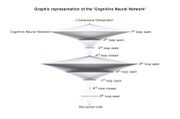

| 11:21, 17 December 2022 | Rete neurale completa1-2.png (file) |  |

372 KB | 1 | |